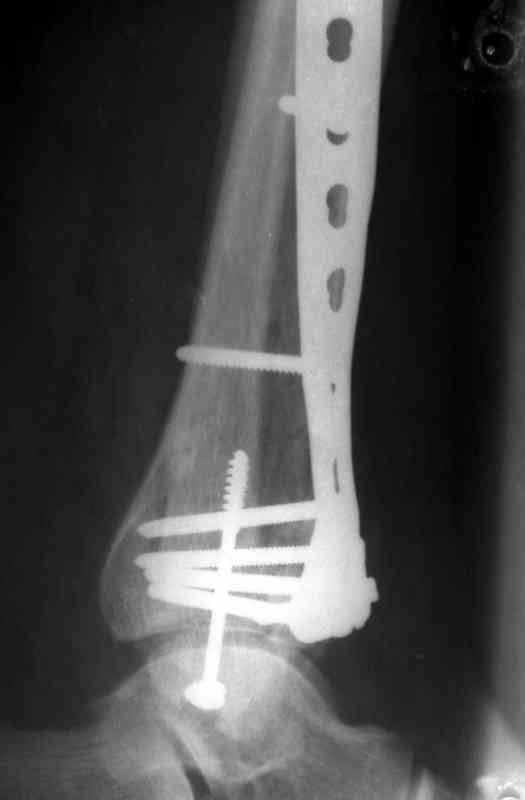

Это типичный перелом пилона, который надп лечить только открыто.Извини те что опоздал к обсуждению, но даже если вы уже оперировали больного по Илизарову это даже лучше.Посылаю картинки.

Посмотрим вроде прошло если понравится напишите расскажу как это сделать.По принципам АО кстати при поступлении сначала восстанавливают длину малоберцовой кости фиксируют пластиной 1/3 трубки потом накладывают аппарат наружной фиксации и через 7-10 дней открыто восстанавливают большеберцовую кость.С уважением Дрягин

На рентгенограммах типичный перелом пилона по типу С-3. есть опыт до 100 открытых опреаций у нас в клинике. 20 примерно в год. Принцип один -все внутрисуставные переломы нуждаются в открытой репозиции и внутренней стабильной фиксации. При поступлении КТ не надо, так как получается только нагромождение костей. Истинной картины нет. Главное восстановить длину малоберцовой кости - это ключ к успеху. При поступлении меньше всего надо думать о сосудистых расстройствах, т.к. сама операция и репозиция даже сначала частичная даёт улучшение сосудитых нарушений. Причём очень быстро. Операция в 2этапа. При поступлении доступ позади наружной лодыжки, причём обязательно. После этого репозиция малоберцовой кости и фиксация пластиной 1/3 трубки под винт 3,5. Дренаж и любой аппарат наружной фиксации. Затем после спадения отёка на 5-7-10 день аппрат снимается и дугообразный разрез спереди от медиальной лодыжки 10-12 см. Главной чтобы расстояние между 1 и вторым разрезом было не меньше 7-8 см. Тогда не будет некрозов лоскутов. Таранная кость используется как матрица на неё укладываются отломки и фиксируются пицами. Ренг-контроль. Отломки лежат все отдельно, но ничего не высыпется. При переломах С-3 всегда нужна костная пластика (из крыла). Фиксация пластиной лист клевера простой или LCP. Гипс не нужен. Дренаж до 48 часов. Операция длится 3-4 часа обязательно без жгута. Посылаю примерно такой же случай.